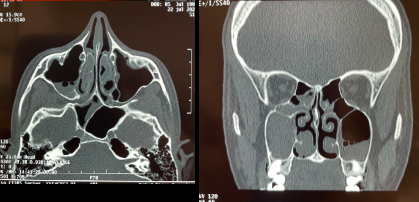

20

Q

¿Qué se ve en esta imagen?

A

Mucocele derecho + espolón

21

Sinusitis Maxilo-Etmoidal DERECHA

*Las bacterias pueden migrar desde otras lesiones